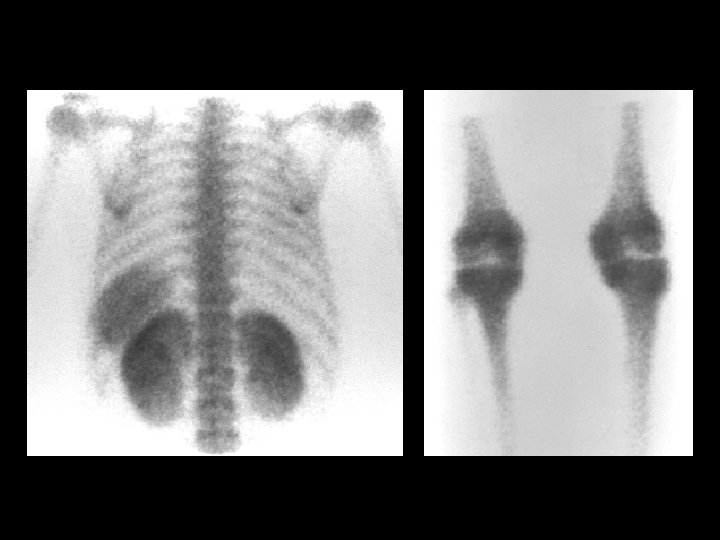

Osteopetrosis • • • Tc-99 m sulfur colloid, i. v. intense liver/spleen uptake, little or none in the bone marrow Trabecular --> compact bone --> Diffuse inc bone density Anemia w/extramedullary hematopoiesis ddx: (adults) – – – myelofibrosis sclerotic metastases renal osteodystrophy multiple myeloma Paget’s